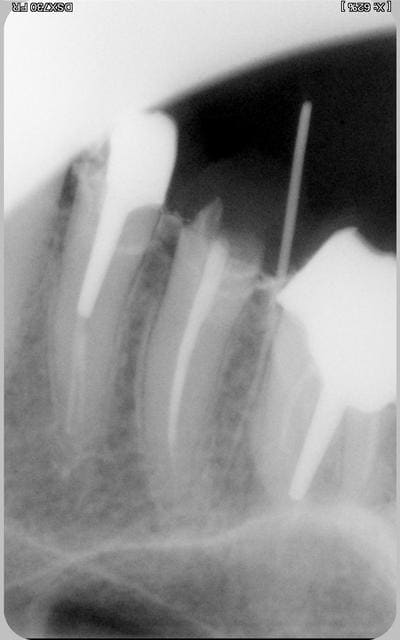

ci joint la radio. je vais poser 3 ccm dessus. l'embetant c'est qu'iol y a une fistule en regard de 15 le ttmt a été repris mais elle persiste. une idée pour savoir d'ou elle vient? (la gutta montrai la 15 ) et commment s"'n dfébarasser?

c'est ce que m'a indiqué le cone de gutta.sur qur c'est paosla 16.

une sortie latérale qui n'est pas obturée.

il me semble qu'il doit être possible "d'améliorer" l'endo de la 15.

Vu le niveau de ta perte de substance, tu as besoin d'une élongation coronaire maousse, qui doit être considérée en fonction du rapport couronne/racine résiduel, de la menace pour la 6 (bizarre la limite de ton IC), et de ta 4 qui a le même soucis.

Une fois que la 5 aura été correctement reprise, si ça persiste tu sera bon pour démonter la 6, dont l'endo de la racine MV n'est quand même pas bien formidable !

me semble quand même que le cone designe l'apex de la 5, y a pas a tortiller, je parie ma blouse.